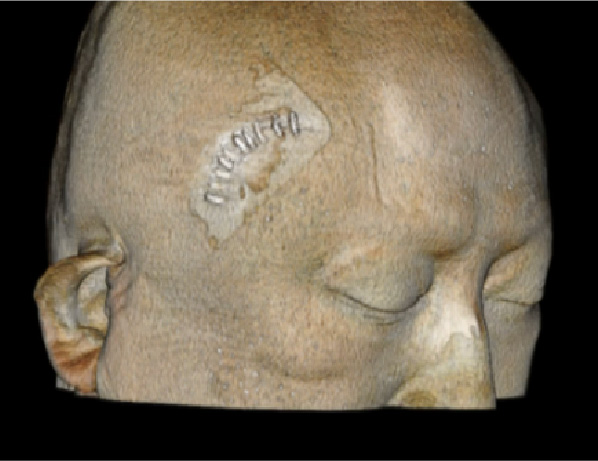

創部画像

なるべく傷が目立たないような工夫をしています。

二重線に沿った傷

手術後1週間程度でほぼ目立ちません